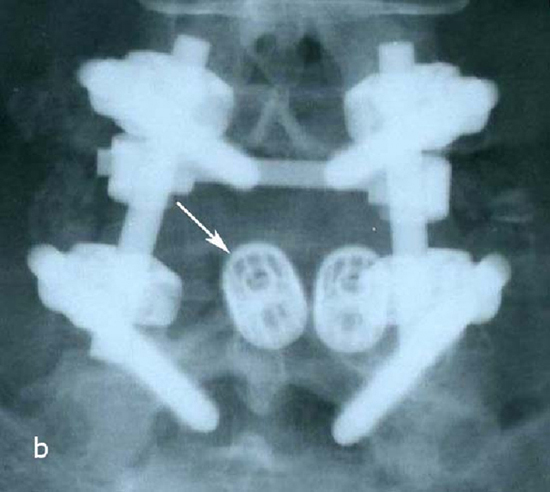

При контрольной рентгенограмме отмечено правильное положение транспедикулярной системы и кейджа на уровне L5-S1 позвонков. (Рис.9)

Рис. 9 a,b. Ренгенограмма поясничного отдела позвоночника в боковой (a) и прямой (b) проекции. Транспедикулярная фиксация L5-S1 позвонков титановой конструкцией канюлированными винтами, межтеловая фиксация позвонков кейджем из PEEK-керамики. Стрелкой указано положение ренген–негативного кейджа, видны титановые метки кейджа.

Рис. 10 a. Ренгенограмма поясничного отдела позвоночника в боковой (a) и прямой (b) проекции. Транспедикулярная фиксация L5-S1 позвонков титановой конструкцией канюлированными винтами, межтеловая фиксация позвонков кейджем из PEEK-керамики. Стрелкой указано положение ренген–негативного кейджа, видны титановые метки кейджа. Рис. 10 b. Ренгенограмма поясничного отдела позвоночника в боковой (a) и прямой (b) проекции. Транспедикулярная фиксация L5-S1 позвонков титановой конструкцией канюлированными винтами, межтеловая фиксация позвонков кейджем из PEEK-керамики. Стрелкой указано положение ренген–негативного кейджа, видны титановые метки кейджа.

Пациенту выполнено оперативное лечение: удаление секвестрированной парамедианной грыжи мп диска L5-S1 слева из минидоступа, миниинвазивная транспедикулярная фиксация L5-S1 титановой конструкцией.